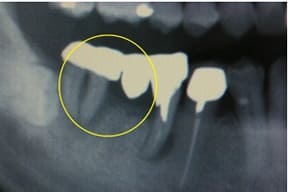

CASE03 臼歯部インプラント ~ブリッジがグラつき始めている~

ブリッジの部分の下顎の骨が吸収をおこし、ブリッジで支えている歯がぐらつき始めている状態。予後を考えた結果、ブリッジで支えることが困難という診断のもと、インプラント治療を施したケースです。